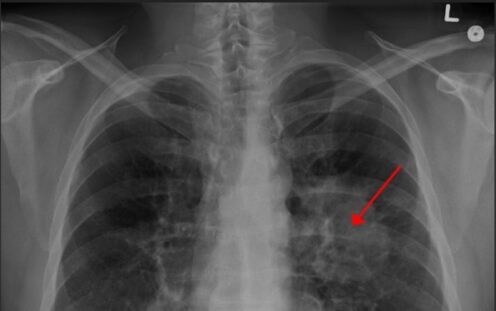

U čtyř lidí ze sta objevíme rakovinu plic

rakovina plic snímek rtg